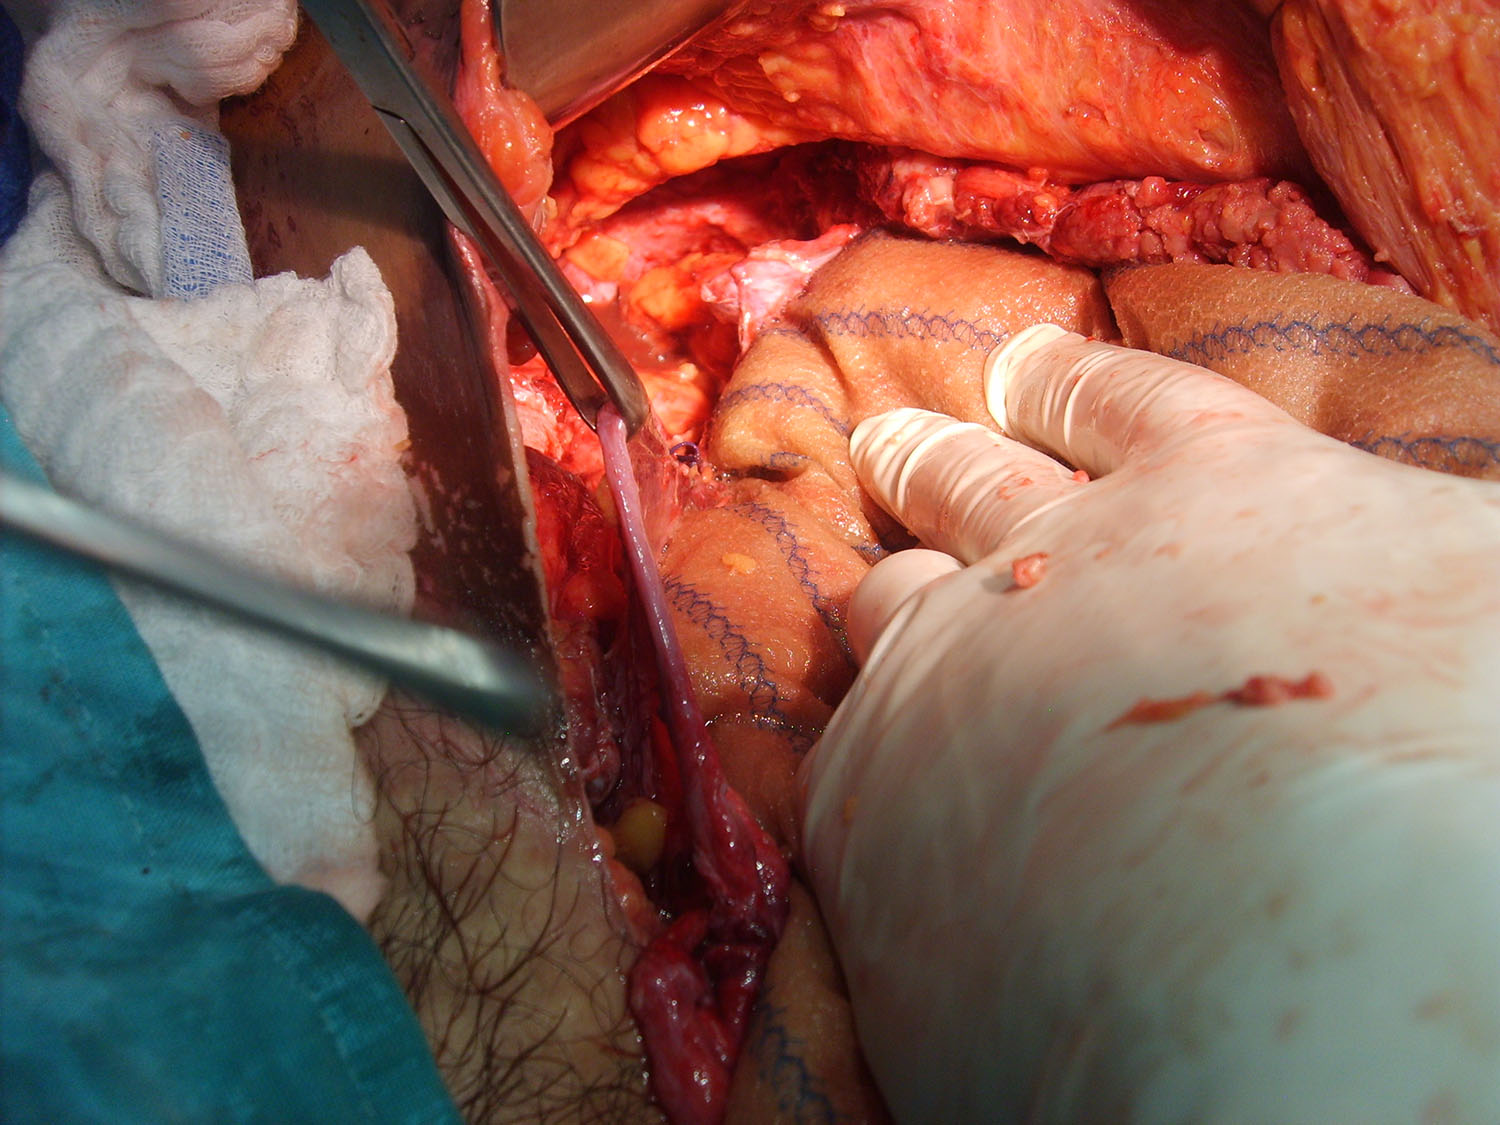

Luego de estabilizada la paciente y al cuarto día de la cirugía del abdomen abierto se lleva la paciente al quirófano. Se constata abdomen con escaso liquido serohemático y asas intestinales sin compromiso vascular por lo que se decide cerrar el abdomen. Es dificultosa la tarea de contener las asas intestinales en la cavidad abdominal debido a la ausencia de pared lateral. Se decide el decolamiento del colon derecho e izquierdo a fin de lograr un espacio para colocar la prótesis, es decir generar un espacio real con el peritoneo para introducir la malla. La sugerencia adecuada del Dr Zorraquino es imposible de realizar, la enferma presenta una retracción importante de los músculos rectos que determinan una cavidad abdominal que supera ampliamente los 900 cm². Se coloca dos mallas de proceed 30 x 30 intraperitoneal fijadas con puntos al espesos total de los remanentes musculares y sobre la misma una malla de prolene 30 x 30 fijada abajo al pubis y a ambas crestas ilíacas y por arriba al plano aponeurótico de los rectos y Oblicuo mayor. Se deja piel y celular abierto. Vuelve a Cuidados Intensivos.

Interesantísimo caso el que nos presenta el Dr. Carlos Cano, bien iconografíado. Se ve en la última foto o así lo interpreto la sección de los músculos rectos y oblicuos.

Posteriormente hemos colocado una prótesis de PPL para dar consistencia a la plastia, incluso tumbando al paciente tras unir los extremos musculares. Se trata de crear una nueva aponeurosis sobre los músculos (Carbonell-Bonafé) y , por tanto, debemos anclarla al marco óseo del abdomen: xifoides-pubis, arcos costales-crestas iliacas. Dejando los laterales por debajo de la aponeurosis del Oblicuo Mayor (OM) anclando el extremo de esta aponeurosis sobre la malla; así conseguimos que la compliance del OM absorba las diferencias de presión intra-abdominal.

Estimado Dr Reyes, aprecio tus comentarios, nosotros no disponemos de mallas biológicas, que si creo hubiesen sido de utilidad en este caso.Con respecto a colocar malla de polipropileno sobre la proceed, fué para tratar de darle más contención al contenido abdominal, por eso esa prótesis la fijamos al pubis y a las crestas ilíacas que estaban totalmente a la vista, según mostramos en algunas fotos.